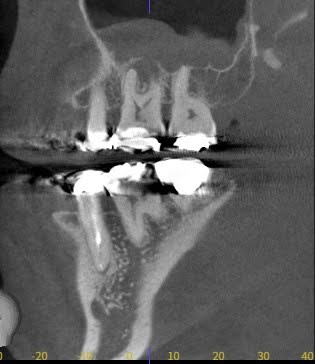

この画像は根尖病変が上顎洞まで波及し、レントゲン上に上顎洞が白い影ができて歯性上顎洞炎になっているものです。

レントゲンやCTを用いて、膿の位置・広がり・骨の状態を正確に把握します。

炎症の程度により、治療計画や通院回数を決定します。